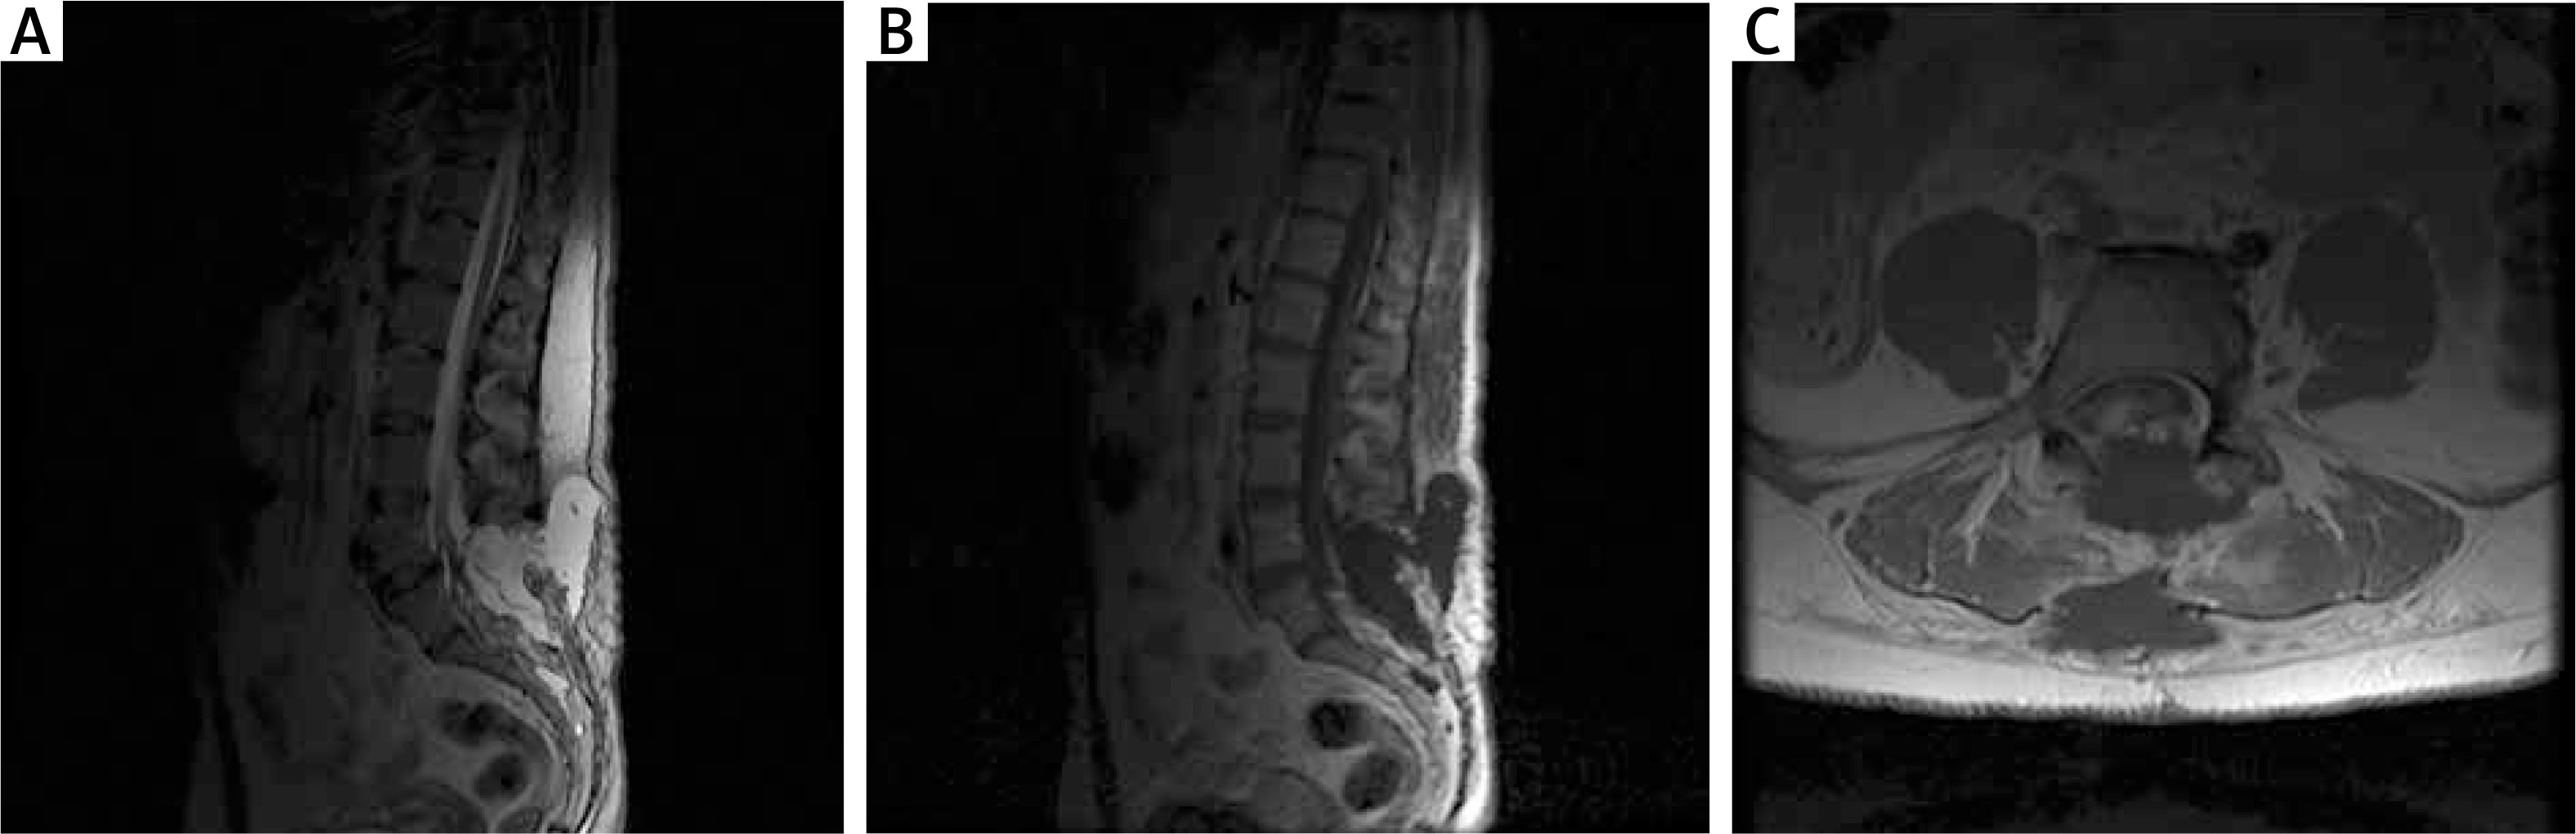

MRI examination of the L/S spine

MRI (1.5 T) showed a thickened terminal strand with a low-lying spinal cone at the S2 level and an accompanying terminal strand fatoma, which argues for the first type of TCS (true TCS, Figure 4).

Figure 4

Preoperative MRI examination of the second patient. A – T1-weighted study showing end-strand adipose and end cone at L5-S1. B – T1-weighted study, coronary sections; visible ratio of the fatoma to the terminal strand. C – axial sections at T2 time; fat pad filling the vertebral canal with visible end thread